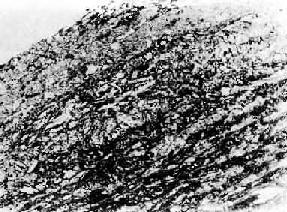

图8-7 主动脉粥样硬化 内膜中形成粥瘤,其中为一些坏死物质及胆固醇结晶,表面内膜呈纤维性增厚 (5)动脉瘤形成:严重的粥样斑块底部的中膜SMC可发生不同程度的萎缩,以致逐渐不能承受血管内压力(张力)的作用而扩张,形成动脉瘤(aneurysm)。另外,血流可从粥瘤性溃疡处侵入主动脉中膜,或中膜内血管破裂出血,均可造成中膜撕裂,形成夹层动脉瘤(aneurysma dissecans)。